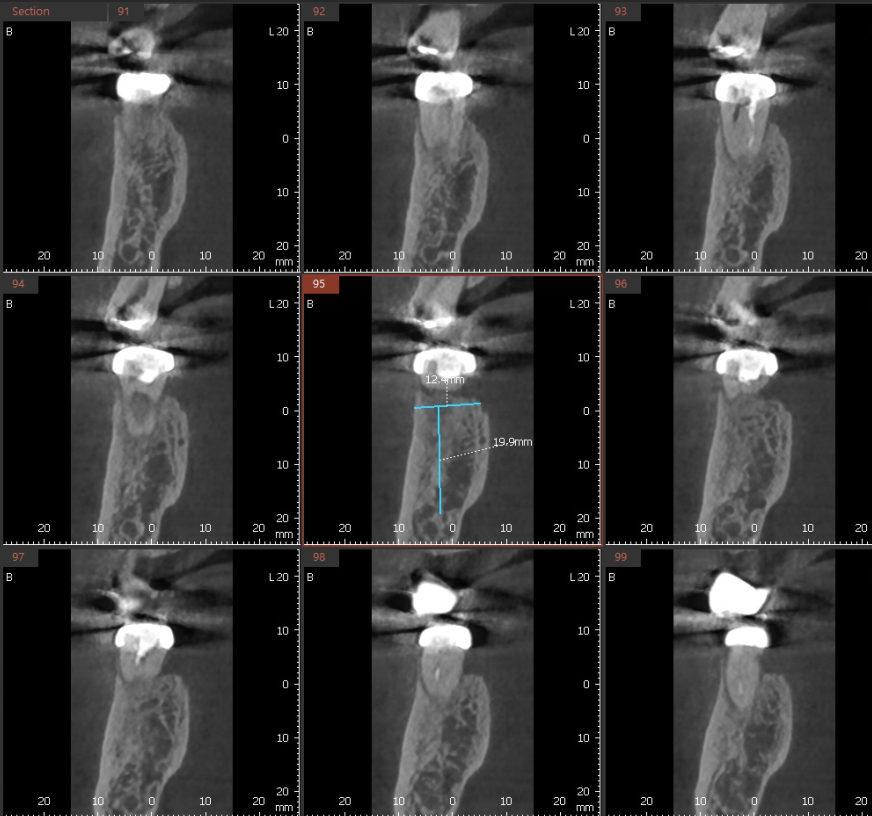

이런 경우 3차원적으로 볼 수 있는 ct를 찍어보는데

치아 뿌리에 금이 관찰됩니다.

금이 간 것을 다시 붙일 수가 없어요.

이럴경우에는 신경치료만으로는 문제를 해결하기 어렵습니다.

금이 점차 치아 내부로 확장되면서 세균이 침투

염증도 일으키고 씹을 때마다 벌어지기도 하고

이럴 경우에는 발치를 고려해야합니다.